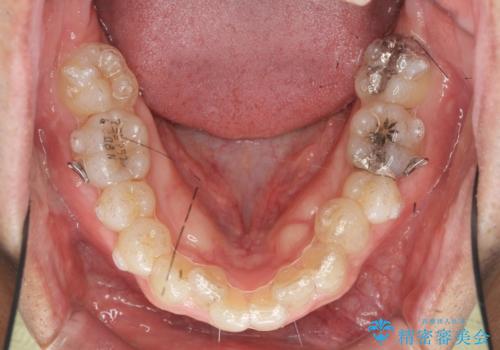

- 矯正装置

- インビザライン

- 3年

- 治療回数

- 10-30回